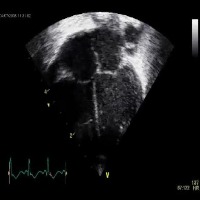

Healthcare and Medical Diagnostics: Utilize the "opt_subopt" model to analyze and categorize ultrasound images, helping medical professionals identify normal, abnormal, and suboptimal cases for better diagnosis and treatment planning.

Medical Education and Training: Integrate the computer vision model into medical education software and simulation tools, enabling students and healthcare practitioners to improve their skills in identifying and understanding different A4C classes in ultrasound images.

Quality Assurance for Ultrasound Equipment: Employ the "opt_subopt" model to evaluate the performance of ultrasound devices by identifying images with A4CSuboptimal and A4CAbnormal results, providing feedback to manufacturers for device improvements and maintenance.

Ultrasound Image Curation and Database Management: Implement the computer vision model in organizing large collections of ultrasound images based on their A4C classes, aiding researchers in finding specific categories of images more efficiently for their studies.

Telemedicine and Remote Consultations: Integrate the "opt_subopt" model with telemedicine platforms, allowing healthcare providers to review and analyze ultrasound images remotely and offer guidance to frontline staff in real-time based on the identified A4C classes.